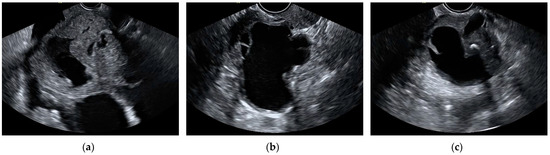

Figure 5.

Still ultrasound images of malignant ovarian masses misclassified as benign by the aggregate model. (a) Endometrioid ovarian carcinoma, (b) high-grade serous ovarian carcinoma, and (c) high-grade serous ovarian carcinoma.